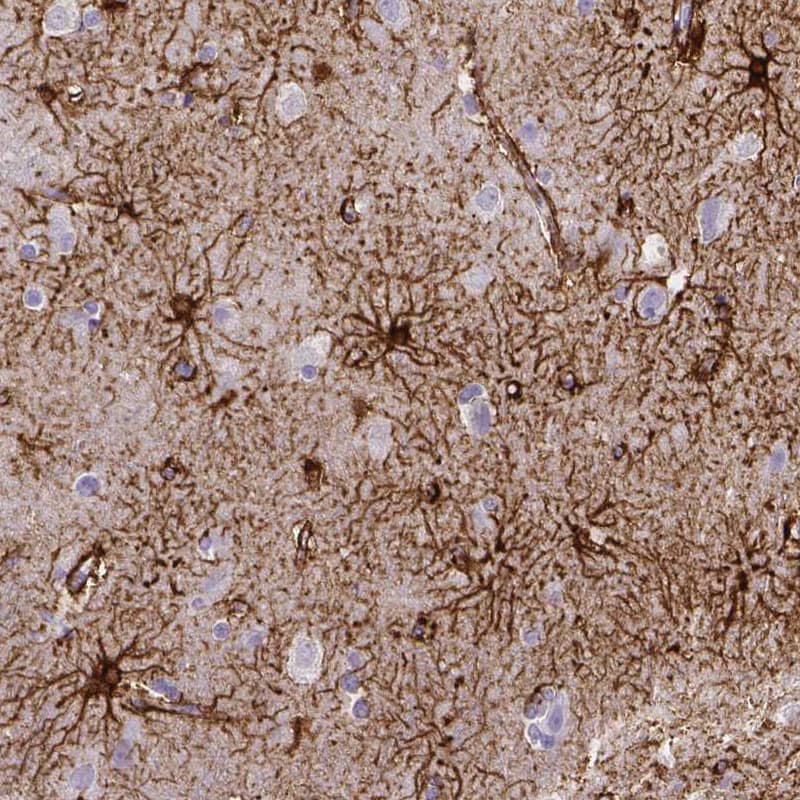

Staining of human cerebral cortex shows strong membranous positivity in astrocytes.